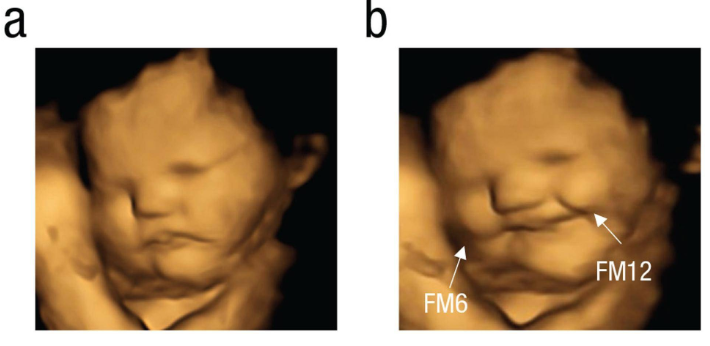

他們利用 4D 超聲技術,捕獲到胎兒的即時表情,嚴謹地證明了:原來我們自打在孃胎裏就不想吃苦!!!

我們都知道,胎兒的正常發育離不開羊水,羊水不僅保護胎兒免受撞擊帶來的風險,還可以讓它體驗母親品嚐到的味道。

這張圖片裏可以明顯看到,左邊的胎兒愁眉苦臉、右邊的卻在眉開眼笑。是因為右邊胎兒的母親吃的是甜甜的胡蘿蔔粉,而左邊吃到的是苦苦的羽衣甘藍。

看來,羽衣甘藍這破玩意連胎兒都覺得難吃。